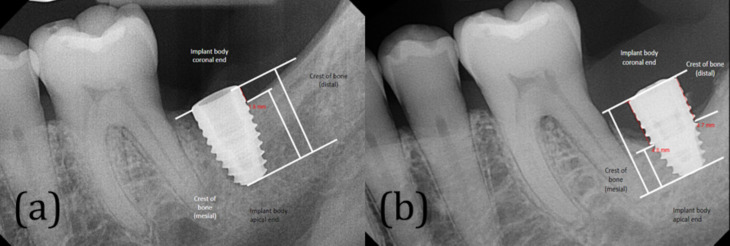

Methods: Clinical notes from patients at the University of Nevada, Las Vegas (UNLV) dental clinics were analyzed using AxiUm™ software. The study included patients with dental implants diagnosed with hypertension, diabetes mellitus, and hyperlipidemia who attended the UNLV School of Dental Medicine clinics from 2012 to 2022. Exclusions were made for patients with acquired immune deficiency syndrome and those with a limited number of radiographs. A search was conducted using keywords such as 'systemic disease,' 'marginal bone loss,' 'dental implant,' 'high cholesterol,' 'hypertension,' and 'diabetes' within the system.